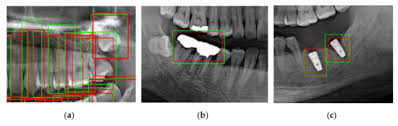

Pdf Tooth Detection And Numbering In Panoramic Radiographs Using Convolutional Neural Networks

Pdf Tooth Detection And Numbering In Panoramic Radiographs Using Convolutional Neural Networks from www.researchgate.net